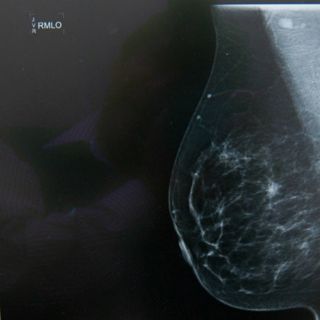

CIUDAD DE MÉXICO (06/ENE/2016).- La Universidad Autónoma de San Luis Potosí (UASLP) estudia diversas técnicas para mejorar el análisis de imágenes médicas, pues la imagenología clínica permite explorar a detalle las principales funciones del cuerpo.

La alumna de la Facultad de Ciencias, Sarahí Hernández Juárez, trabaja para realizar comparaciones cuantitativas de métodos de segmentación de imágenes médicas, para lograr organizar distintos tipos de estructuras del cuerpo.

"El objetivo inicial del proyecto era comparar métodos de segmentación en el ámbito clínico para lograr segmentar distintos tipos de estructuras de interés", dijo Hernández en una entrevista con la Agencia Informativa del Consejo Nacional de Ciencia y Tecnología ( Conacyt).

"Después se complementó con la comparación por parte de un experto clínico, para verificar la eficiencia de los métodos de segmentación conocidos, en este caso enfocado en el tratamiento de radioterapia", añadió.

Los métodos que se aplicaron fueron K-means, Otsu y Chan-Vese para la segmentación de imágenes de pulmones y un tumor cerebral.

El análisis cuantitativo constó del cálculo de índices de precisión que comparan la segmentación obtenida por cada método con otra de forma tradicional por un especialista clínico.

Los índices adquiridos fueron la distancia simétrica media, la distancia máxima, el porcentaje de distancias mayores a la dimensión del pixel y el índice de superposición.

Los resultados arrojaron que para la segmentación de los pulmones los algoritmos se comportan de manera similar, pero en el caso del tumor, el método de Chan-Vese es preferible.

"Podemos decir que los métodos de segmentación nos pueden dar mucha información característica de las estructuras, por ejemplo en este caso se evalúo el tumor de un cerebro", dijo la encargada del proyecto.

"Así que se puede aplicar en el área de radioterapia y darle un sentido más real", añadió.

Los autores esperan en trabajos futuros complementarlo con otros métodos de segmentación de imágenes médicas para aplicaciones en la localización y tratamiento de tumores.